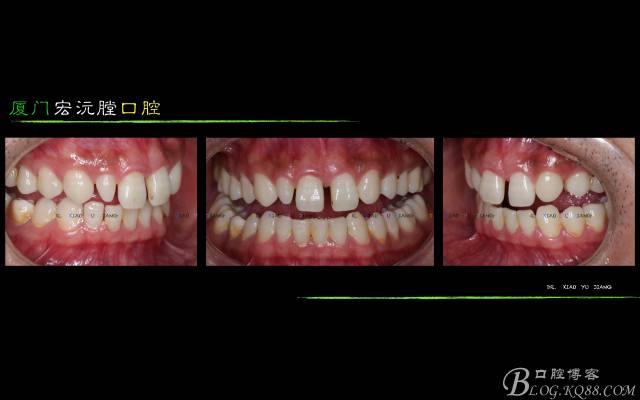

主訴:上前牙有縫隙,不美觀,要求改善

現(xiàn)變史:從小門牙稀疏有縫至今

檢查:上前牙稀疏有縫,中線向左偏斜,22缺失,前牙二度深覆,11與12之間1.8mm縫隙,11與12之間0.7mm縫隙,12與13之間0.8mm縫隙,23與24之間1mm縫隙

診斷:22先天性缺失;上前牙散在間隙

1、面相及口內(nèi)照